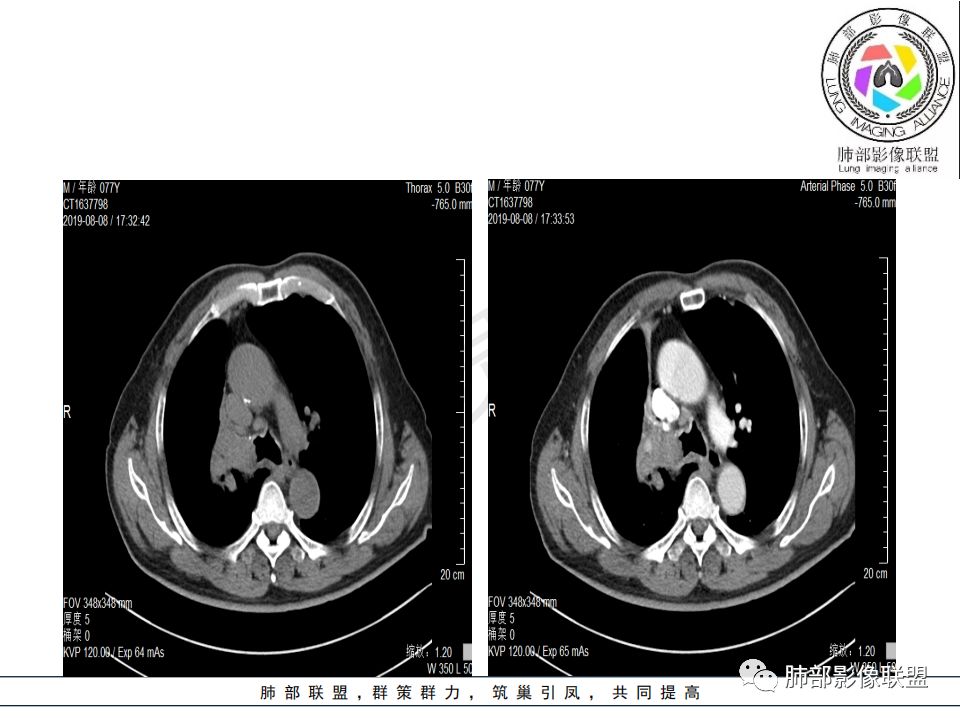

病史:男.77岁,咳嗽1月;干咳,少许白痰,无发热,2013胃癌术后,角蛋白24.65(0-3.07),SCC和proGRP不高;

影像:影像右侧大支气管阻塞,临床没有症状或很轻微,要想到胃腺癌转移;胸壁代偿好,透亮度稍低不明显,慢性过程;34.8-52.5HU,主病灶支气管前壁另有1结节,都做成增强两期了,动脉期较平扫有强化;

诊断:多发,转移,无淋巴结及胸腔积液;

鉴别:原发鳞癌。

晨读:患者老年男性,以咳嗽一月就诊,少量白痰,胸CT:纵隔右移,右肺体积缩小,气管下段管壁可见结节样改变,气管软骨变形,气管下段及右主支气管可见新生物向管壁浸润,并向管腔外生长,右上肺肺不张,但不张边缘可见病灶呈膨胀性生长,可见分叶,增强后强化明显。考虑:肺部恶性病变(鳞癌?)